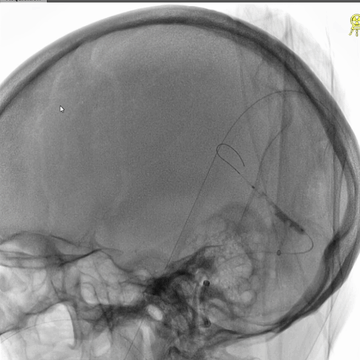

中间管造影:上矢状窦中后部和右侧横窦-乙状窦血液引流可。

微导丝微导管再次超选直窦,造影示直窦近段狭窄。

3*30mm球囊再次扩张直窦近段,辅以球囊滑动技术。

球囊扩张直窦后造影:直窦近段仍见狭窄。

微导管造影示:右侧横窦-乙状窦仍见明显狭窄。

直窦再次微导管造影:直窦血液引流可。

6*30mm球囊扩张右侧横窦-乙状窦和颅底位置颈内静脉,辅以球囊滑动技术。

介入治疗后右侧颈动脉造影:上矢状窦、直窦和右侧横窦-乙状窦均见显影,右侧横窦局部狭窄明显。